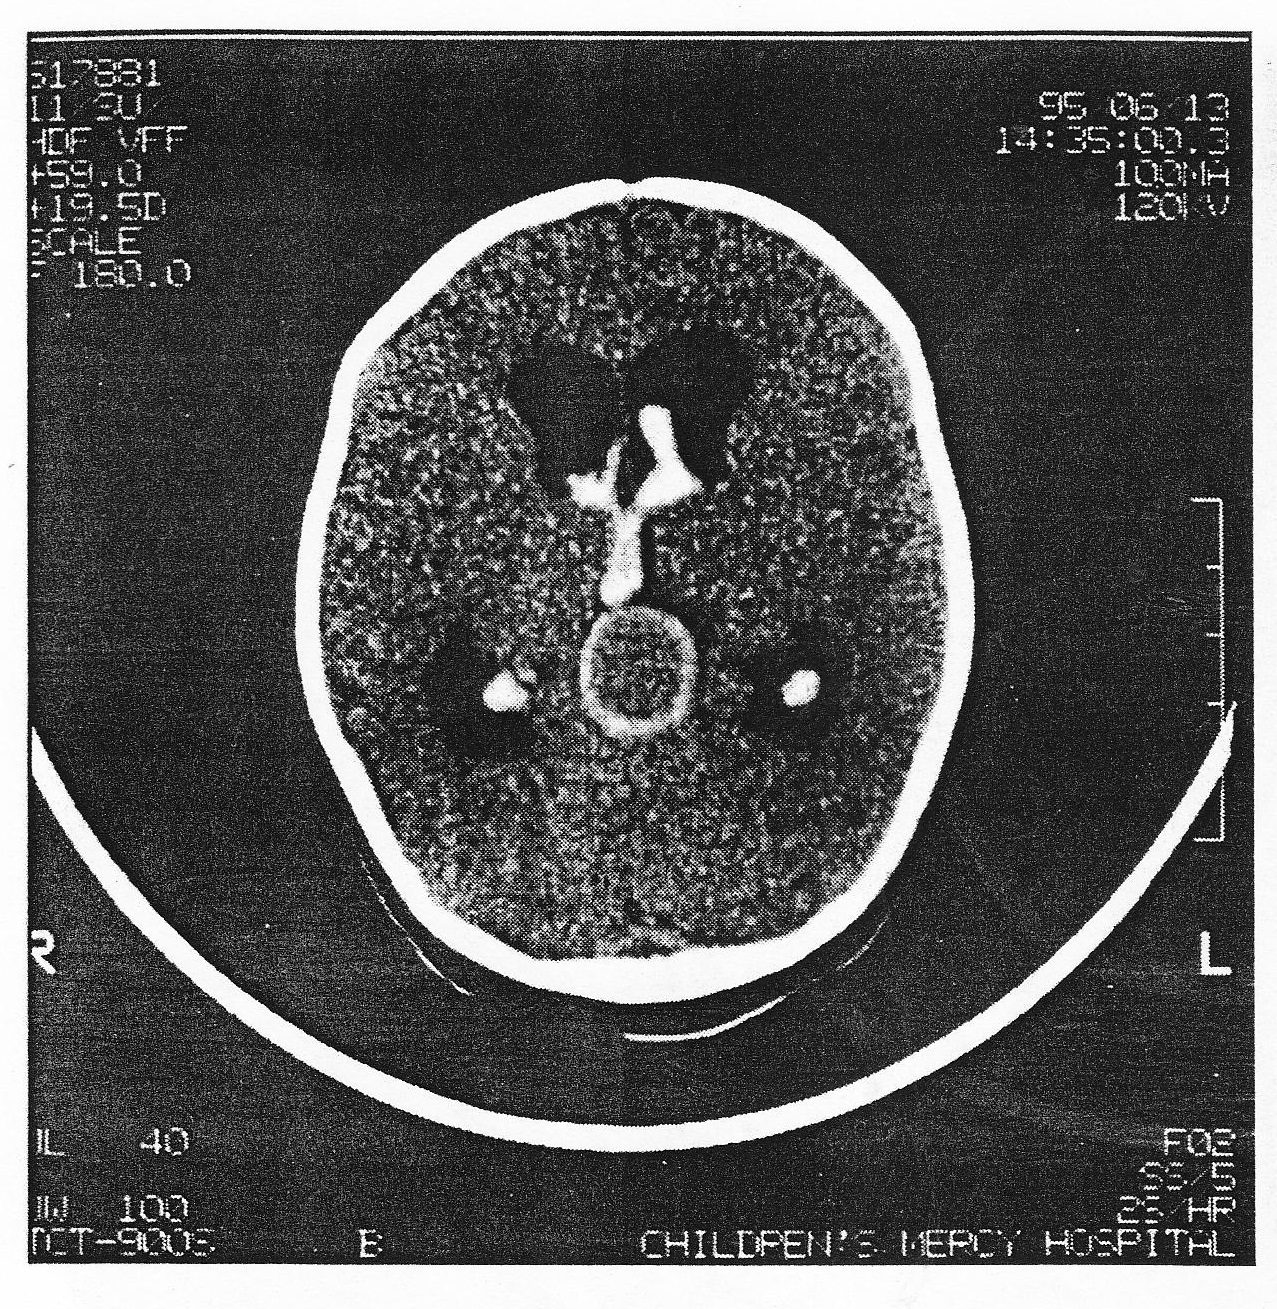

A new born child has seizure and overt heart failure. The child was well at the time of her birth. The anterior fontanelle is now full. A CT scan demonstrates hydrocephalus and a malformation (Figure 39). Based on the clinical history and CT finding, the NOST LIKELY diagnosis is:

A. Tectal glioma

B. Giant basilar aneurysm

C. Vein of Galen fistula

D. Hydrocephalus from obstructive pineal tumor

E. Brain abcess

A new born child has seizure and overt heart failure. The child was well at the time of her birth. The anterior fontanelle is now full. A CT scan demonstrates hydrocephalus and a malformation (Figure 39). Assuming this neonate’s condition becomes stable after medical treatment and has persistent borderline heart failure, OPTIMAL therapy would be:

A. Observation

B. Decadron, followed by surgical excision of the tumor

C. Surgical clipping of vein of Galrn aneurysm

D. Transvenous or transerterial embolization

E. Ventriculoperitoneal shunting